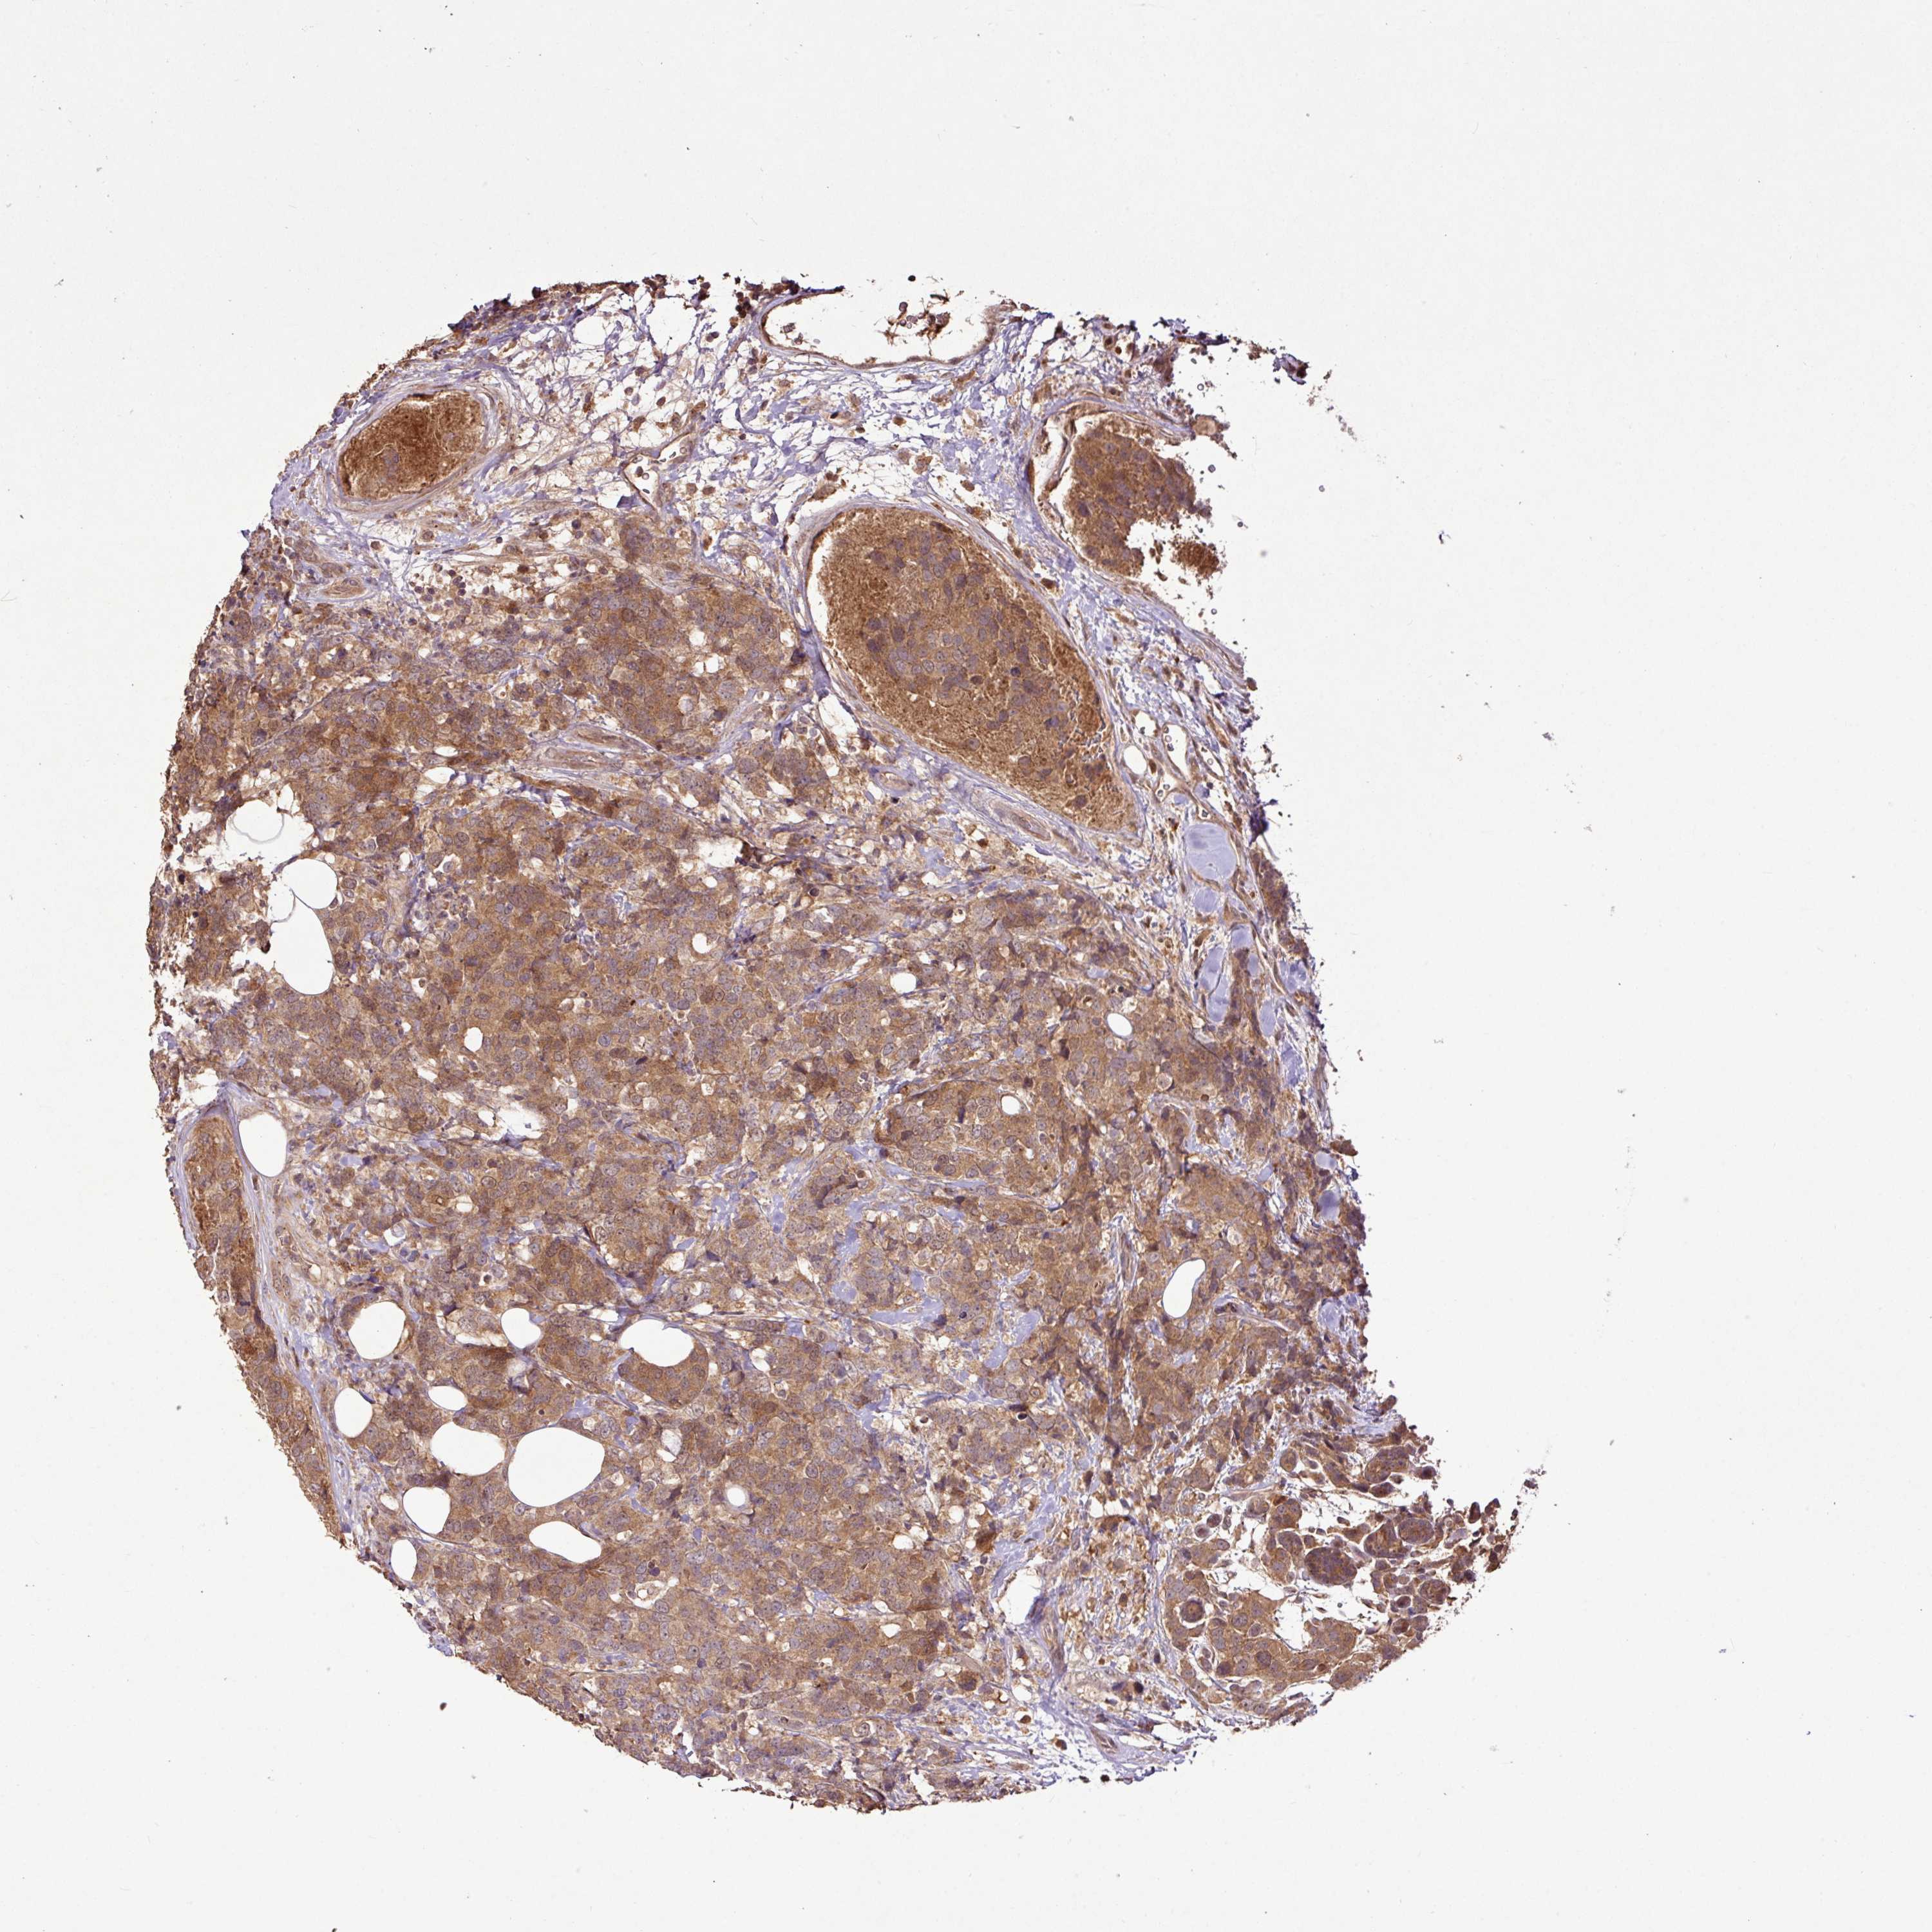

CANCER BREAST CANCER Show tissue menu

BRCA TCGA BRCA VALIDATION PROTEIN EXPRESSION